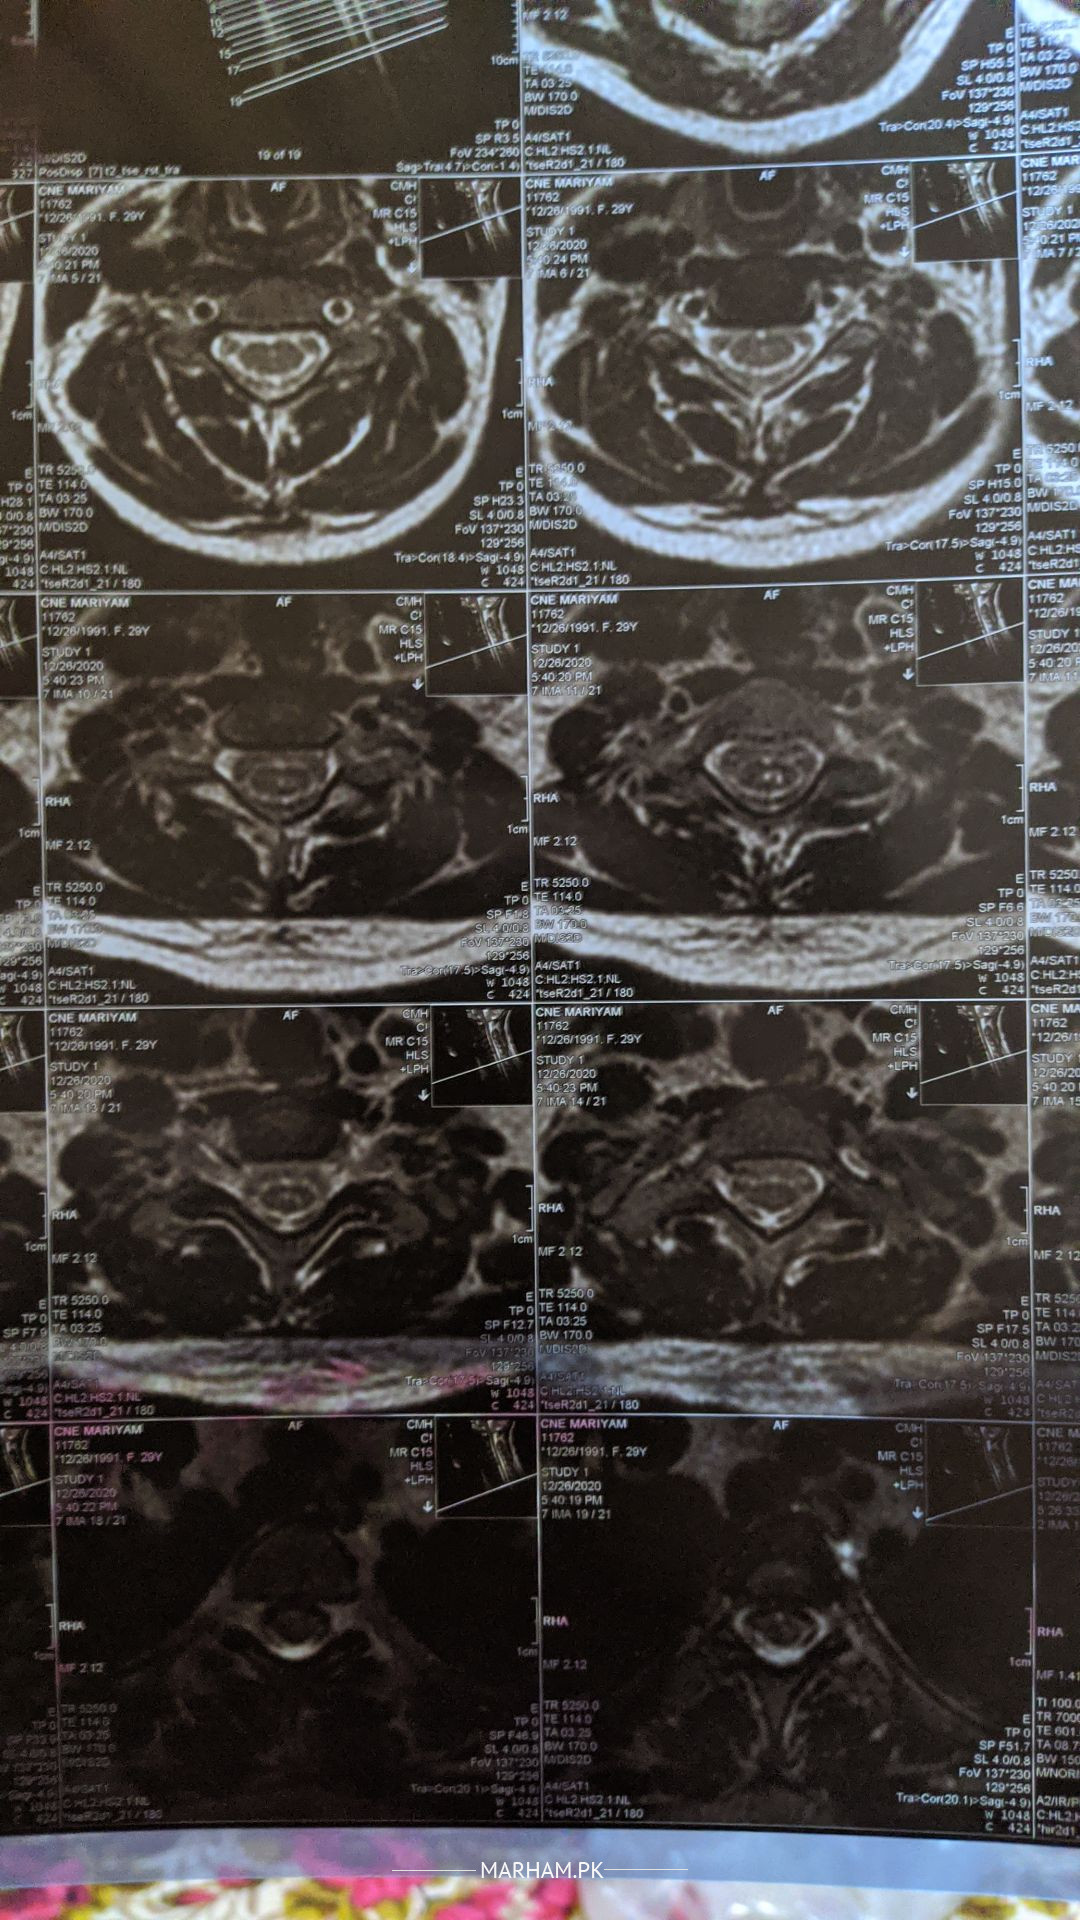

I am having severe pain in neck. Weakness in my right arm and hand. strange sensation in both right limbs with weakness. I am unable to hold or lift any object with my hand, I feel my hand and arm is getting tired and it pain in my neck. If I forcefully do any work with right hand and arm, my lower limb also get affected like problem in walking. I uad done my MRI in 2020, I am attaching it Please suggest me further and guide me why is this happening.

this MRI minor changes at C5-6

previously compression was not too much but there was straightening of the cervical spine but now it may have compressed that's why causing pain in arm as well as weakness. physical examination is required to make a definitive diagnosis

I have uploaded the MRI report.

it also tells about Syrinx.

please guide me is there anything to worry about.